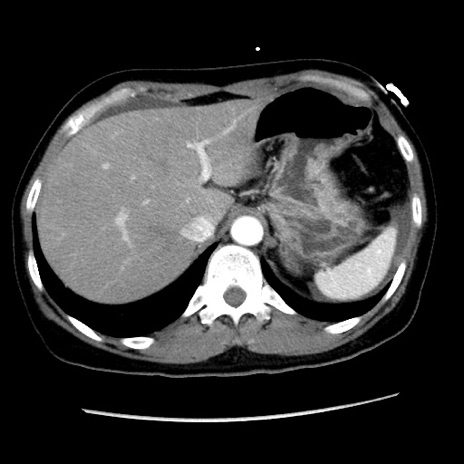

症例10(横断像)

【症例】 50歳代女性

【主訴】 腹痛

【現病歴】前日生レバーを食べた。今朝に排便あり。 昼前に突然発症の腹痛を生じ、当院救急外来を受診した。

【身体所見】 意識清明、腹部:平坦、軟、下腹部やや左を中心に圧痛・反跳痛あり、筋性防御あり

【データ】WBC 7800、CRP 0.07